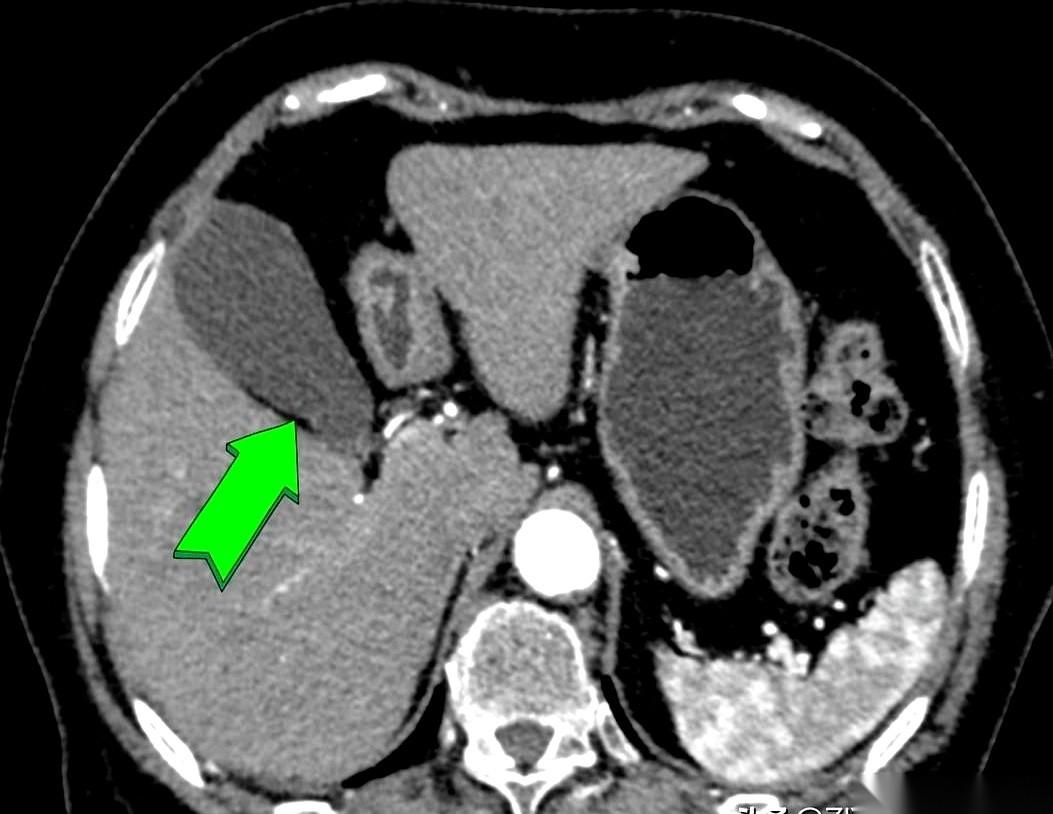

我跟你讲个事儿,绝了。 一个阿姨,肚子疼了20天,跑去做CT,报告白纸黑字写着:胆囊没毛病。 可她就是疼啊!转头又去做了个B超,好家伙,B超上清清楚楚,一堆石头。 同一个胆囊,同一个时间,俩机器,两种命。 这找谁说理去? 后来才知道,石头这玩意儿,也分“三好学生”和“隐形刺客”。 阿姨得的那种,叫胆固醇结石。说白了,就是一肚子“油”结晶了。 这东西密度低,跟胆汁儿差不多。 在普通CT眼里,它俩就是一伙儿的,跟透明的冰块扔进了白开水里一样,根本看不出来。CT报告当然写“没事”。 但B超不一样,它靠的是耳朵,是声波。 石头和液体,在它听来,动静完全不同。一下就给揪出来了。 所以啊,有时候真不是机器骗你。 是你身体里那个“对手”太狡猾。 这事儿给我最大的感触就是,别太迷信一张报告。 尤其是当你的身体还在持续发出警报的时候。 你的疼,你的难受,才是最真实的报告。 机器是死的,人是活的。多问一句,换个法子查,可能就是天壤之别。 千万,千万要信你自己的身体。 它不会骗你。